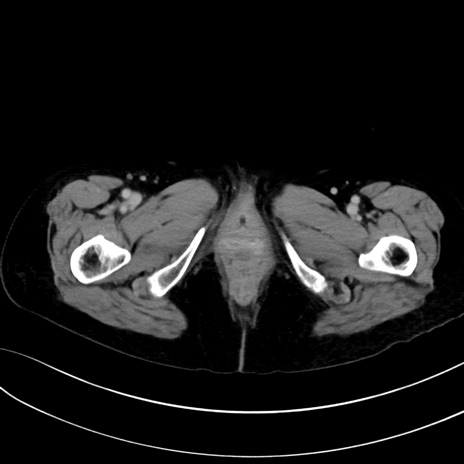

症例13 CT(横断像)1日半後